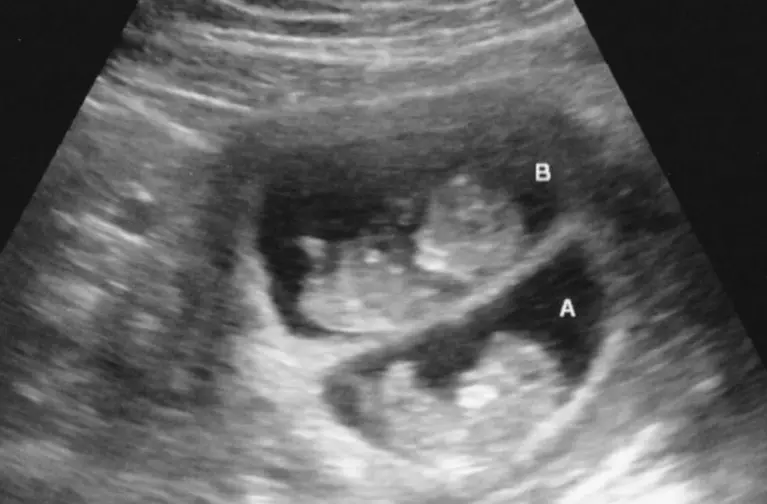

Besides simply taking to the training quickly, something else began occurring. It seemed as if Lueder was a metaphorical “lightning rod” for discovering twins on ultrasound.

“We had a large number of models at PHI who were pregnant with twins,” Brown remarked of the training in Columbus. “This was by coincidence, but by the third day had become quite comical to find yet another set of twins on

ultrasound.”

“It was God’s timing giving me clarity that this (PHI training) was the proper program, and it was the right training to go with,” recalled Lueder. “Then we saw several sets of twins in the training of various gestations.”

“When we went home, we shadowed stenographers for a while for more practice, to gain further understanding of the equipment and doing correct measurements,” she continued. “I had one set of twins a few weeks ago of seven weeks gestation with a teenage mom.”

In one day, they actually saw two clients who were pregnant with twins and were in the center at the same time.

“We did have a set of twins a month ago (19 weeks gestation),” Lueder said, “the client was very determined to have an abortion but changed her mind after seeing the ultrasound.”